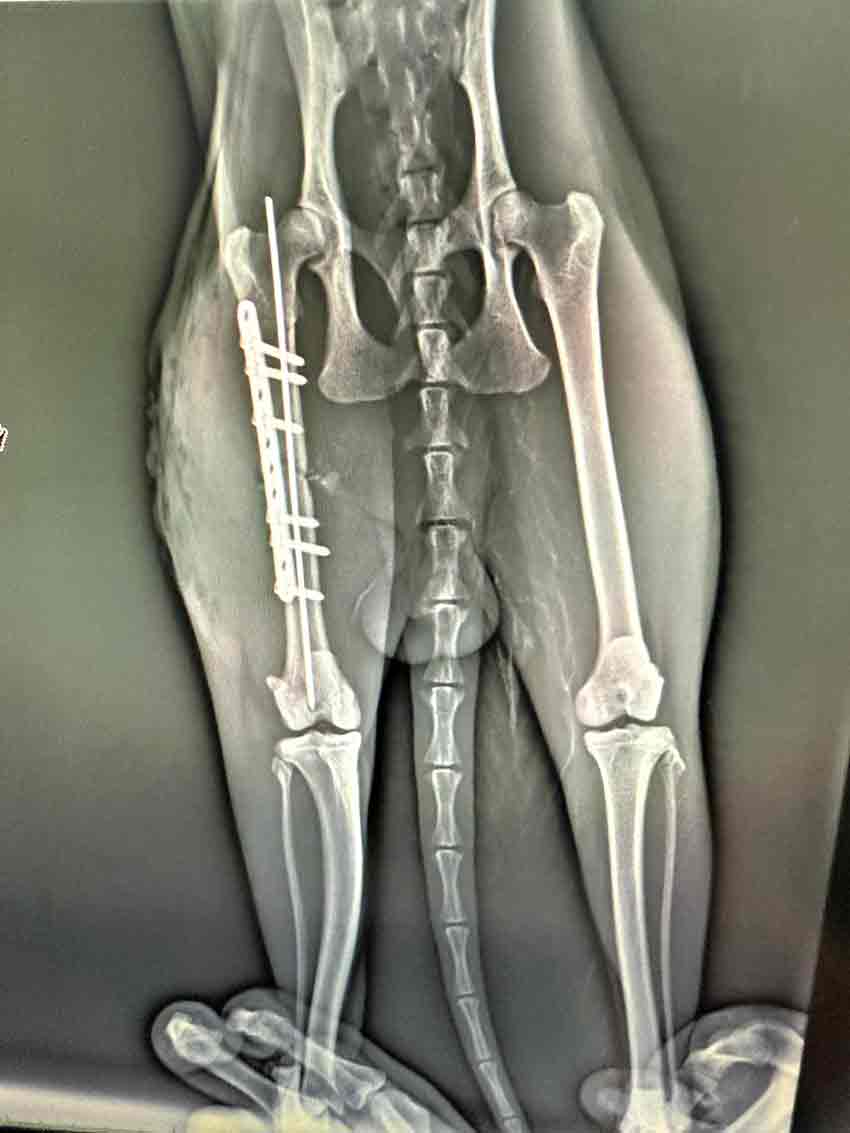

Zonguldak'ta evin balkonundan düşen kedi yaralandı. Ameliyata alınan kedi tedavisi yapılarak sağlığına kavuşuyor.

Veteriner Hekim Koç, Havaların ısınmasıyla birlikte, evi havalandırmak amacıyla camlar ve kapılar açılıyor. Ancak bu durum, ne yazık ki kedilerimizin camdan atlaması ya da kapılardan kaçmasıyla sonuçlanabiliyor. Kaçan kediler sokakta travmaya maruz kalabiliyorlar. Camdan atladıklarında ise travmalar çeşitli şekillerde ortaya çıkabiliyor; kırıklar hatta Allah korusun ölümle sonuçlanabilecek kazalar meydana gelebiliyor. Bu nedenle yaz mevsiminde camlar açılırken kontrollü olunması ya da sineklik kullanılması gerektiğini, her yıl olduğu gibi bu yıl da yeniden hatırlatıyoruz. Bu hastamız da travma sonucu yani bir trafik kazası nedeniyle kaçamamış ve maalesef kırık oluşmuş. Yaptığımız ameliyatla kırık başarıyla tedavi edildi. Şu an genel sağlık durumu iyi şeklinde konuştu.